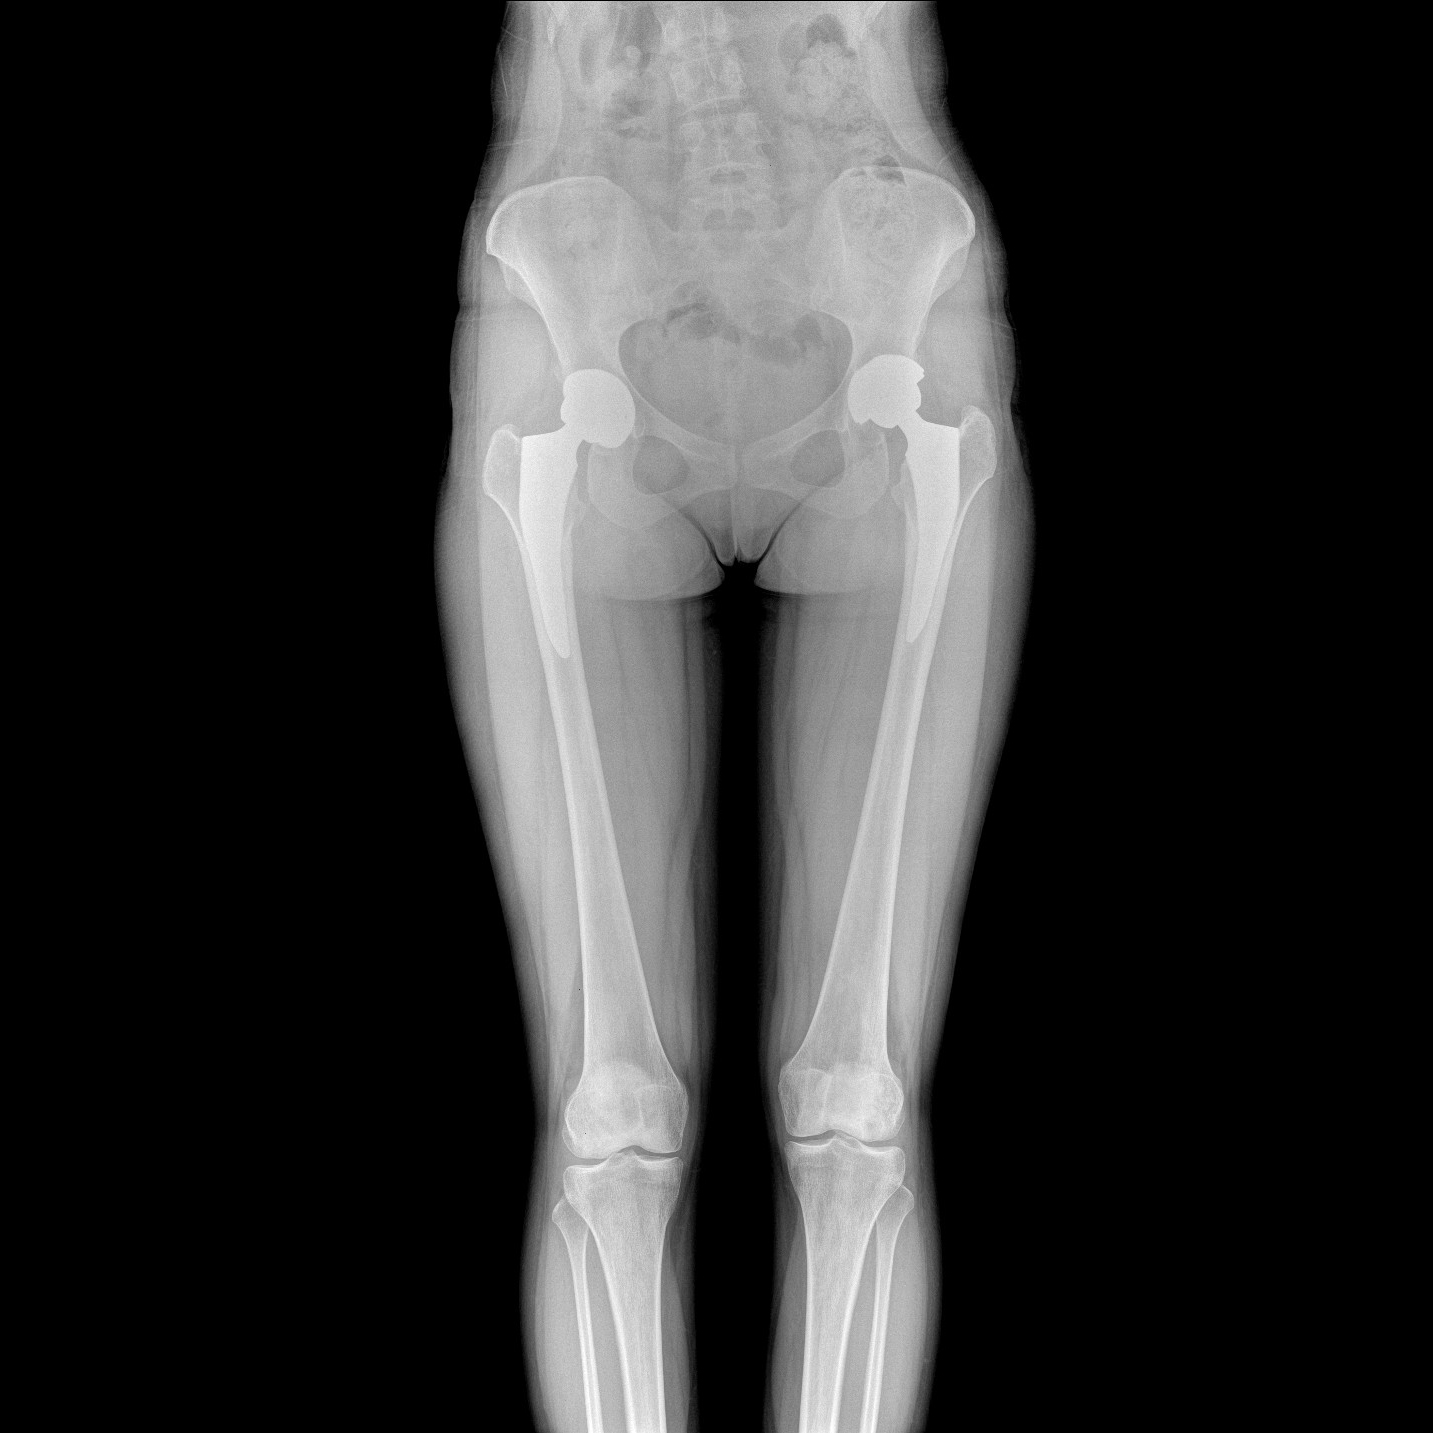

支持全脊柱攝影、雙下肢攝影、脊髓造影、復雜創(chuàng)傷、人工關節(jié)置換、關節(jié)損傷的修復重建等大視野臨床應用

17"*34"有效視野,一次成像不拼接。相較于多張攝影再軟件拼接的DR設備,PLX8600解決了拼接圖像存在密度不均勻,拼接處圖像配準和放大效應等問題,給臨床帶來了大視野影像解決方案,可一次性覆蓋全脊柱或雙下肢影像。